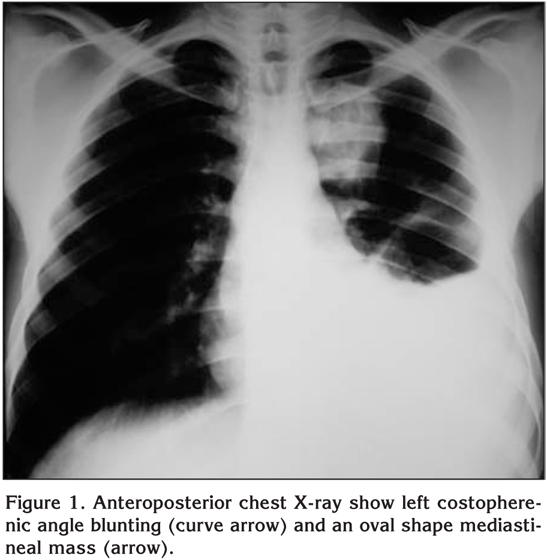

Originally, the patient went to emergency in nearby hospital, and a chest roentgenogram revealed the presence of costopherenic angle blunting and an oval mass in the left mediastinum (Figure 1). On chest drain insertion, a total of two liters of blood was drained. Subsequently, the patient received four units of packed red blood cell (RBC) transfusion and two units of fresh frozen plasma (FFP). After he was stabilized, he was transported to our tertiary center for further work-up.

Figure 1

We present the case of a 30-year-old man with no past history of disease or recent trauma, who was seen in the emergency room after developing sharp pain in the left hemithorax. Chest roentgenogram showed costopherenic angle blunting and an oval mass in the left mediastinum. A computed tomographic scan showed extrapleural mass with coarse calcifications and pleural effusion, confirmed by magnetic resonance imaging. The tumor was biopsied and removed during thoracotomy. The pathology reported revealed chondrosarcoma, which is a rare cause for a spontaneous massive hemothorax. Invasion of the intercostals vessels by the tumor was the probable cause of hemothorax in this patient.